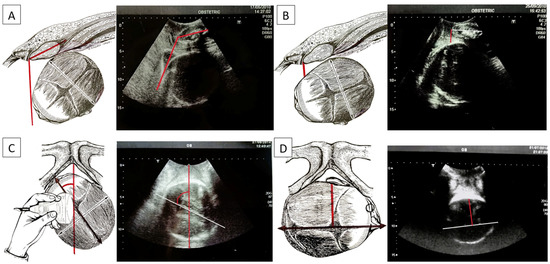

The AoP is the angle identified using a line passing through the central part of the pubic symphysis and another tangent to the fetal skull via longitudinal scanning (Figure 3A). Using a geometric model, Barbera et al. [14] developed an algorithm to assign a specific set of theoretical intervals of angles at the mid-point of a line drawn between the ischial spines (at zero station: lower angle: 96°, mean angle: 99°, upper angle: 102°) and at the other intervals of angles at the other clinical stations (−5 to +5). This measurement, initially termed the “angle of descent”, is now scientifically referred to as the angle of progression (AoP). Upon reaching full dilatation in all women, an AoP greater than 120° was consistently associated with head engagement, as determined via clinical examination. Notably, in all instances of vaginal delivery, there was a uniform increase in the AoP, and spontaneous delivery occurred in 90% when the AoP exceeded 120° [15].

The HSD is evaluated via translabial sonography in a lithotomy position of the patient and on the midsagittal scan. On this view, two landmarks are identified: the maternal pubic symphysis and the fetal head. The HSD is the minimum distance between the lower margin of the maternal pubic symphysis and the fetal parietal bone (Figure 3B). If HSD > 20 mm, the head is not engaged. If HSD < 20 mm, it is engaged, having reached at least the ischial spines. For values less than 10 mm, the head is between +2 and +3, according to the ACOG classification. A low HSD value associated with other parameters (high angle of progression and midline angle <45°) depicts a good delivery outcome [17]. In our database, our algorithms were found for HSD cut-off values of 19.5 mm between non-ICDs for HSD < 19.5 mm and ICDs for HSD >= 19.5 mm.

In the MLA, the angle formed by the fetal head midline (the echogenic line between the two cerebral hemispheres) and the anteroposterior diameter of the pubis is measured, known as the “midline” angle (Figure 3C). This midline angle measurement appears to correlate with the clinically assessed station, particularly in fetuses with an occiput anterior position. If the midline angle is less than 45°, the station is typically ≥+2 cm in many cases. Conversely, in fetuses with a midline angle >45° or one that is not clearly measurable, the clinical assessment often indicates the head station as <+2 cm from the ischial spines. The midline angle value has also been shown to be helpful in predicting the success of operative vaginal delivery, as no failures were reported in fetuses with an occiput anterior position when the midline angle was ≤45°. When the MLA is less than or equal to 45°, internal rotation has occurred and the head has rotated. If it is greater than 45°, internal rotation has not occurred [18].

Asynclitism is evaluated via vaginal digital examination, but the AD can be detected via intrapartum ultrasound, which improves the diagnosis through a transabdominal ultrasound that diagnoses the squint sign (which is the visualization of only one fetal orbit, which is a landmark that indicates that the head is twisted in the birth canal). With translabial US, anterior asynclitism is defined when the midline shifts towards the sacrum, while posterior asynclitism is defined when the midline shifts towards the pubis. To evaluate the degree of asynclitism, the distance in millimeters between the midline and the presented parietal bone was evaluated using translabial ultrasound in the longitudinal plane (Figure 3D). A moderate degree of asynclitism is considered a normal adaptation of the fetal head in the birth canal, and it results in normal labor and spontaneous delivery, specifically when the fetal head in the occiput anterior position engages with an anterior asynclitism. High-grade asynclitism can be associated with maternal and fetal complications, the most common of which are arrest disorders of the fetal head during descent into the birth canal [19,20]. In our database, our AIDA algorithm identified an interval cut-off for AD, with a lower value of 65.5 mm and an upper value of 70.5 mm for ICDs for AD >= 70.5 mm and non-ICDs for AD < 65.5 mm.

All these ultrasonographic parameters and rotations in the fetal position are depicted in Figure 3.

Figure 3. (A) Angle of progression (AoP): the drawing on the right and the US photo on the left show the AoP (red line) with the fetal head in the occiput anterior position; (B) fetal head–symphysis distance (HSD): the drawing on the right and the US photo on the left show the HSD (red line) with the fetal head in the occiput anterior position; (C) midline angle (MLA): the drawing on the right and the US photo on the left shows the MLA with the fetal head in the left occiput posterior position (white/black line: midline, the echogenic line between the two cerebral hemispheres; red line: anteroposterior diameter of the pubis). Longitudinal translabial sonography detected the MLA; (D) asynclitism degree (AD): the drawing on the right and the US photo on the left show the AD with the fetal head in the right occiput posterior position with anterior asynclitism (white/black line: midline, the echogenic line between the two cerebral hemispheres; red line: anterior asynclitism degree, perpendicular to the white/black line).